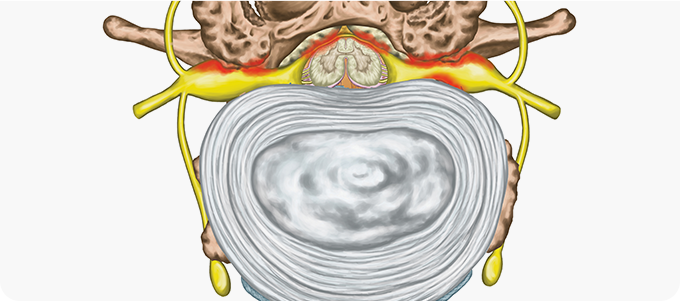

척추관 협착증의 치료방법

척추관 협착증의 치료는 신경 압박을 완화하고 통증을 줄이며 척추 안정성을 강화하는 데 초점을 둡니다.

약물치료와 물리치료로 염증과 부종을 줄이고, 운동치료로 척추 주변 근육을 강화합니다.

심한 경우 수술적 방법으로 척추관을 확장해 신경 압박을 해소합니다.

신경성형술 사진

2

내시경 신경성형술

특수한 카테터를 사용하여 신경 주위의 유착을 풀고 염증을 완화하는 비수술적 치료법입니다. 이 방법은 신경 압박을 해소하여 통증을 줄이고, 허리디스크와 척추관 협착증 등 다양한 신경통 치료에 효과적입니다. 절개가 필요 없으며 회복 기간이 짧아 부담이 적습니다. 다만, 환자 상태에 따라 적합 여부를 전문의와 상담하는 것이 중요합니다.

• 내시경적

치료

• 효과적인

통증 완화

• 다양한 질환

적용 가능

• 빠른

일상생활 복귀